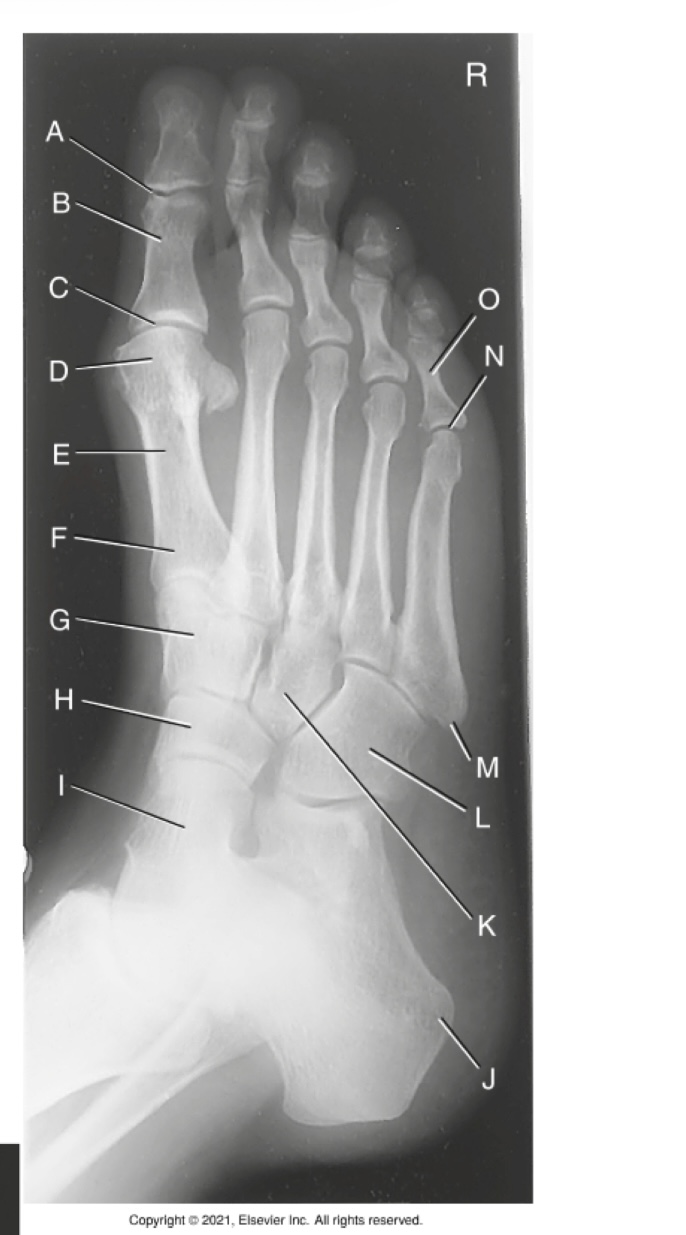

A

Interphalangeal joint of 1st digit

B

Proximal phalanx of 1st digit

C

Metatarsophalangeal joint of 1st digit (MTP joint)

D

Head of 1st metatarsal

E

Body of 1st metatarsal

F

Base of 1st metatarsal

G

Second/ intermediate cuneiform

H

Navicular

I

Talus

J

Tuberosity of calcaneus

K

Third / lateral cuneiform